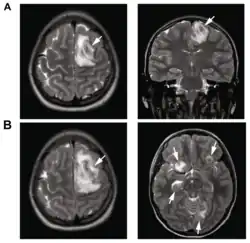

| T2-weighted MRI showing a necrotic brain abscess caused by Acanthamoeba. | |

B: T1-weighted MRI showing expansion of the brain infection 4 days later